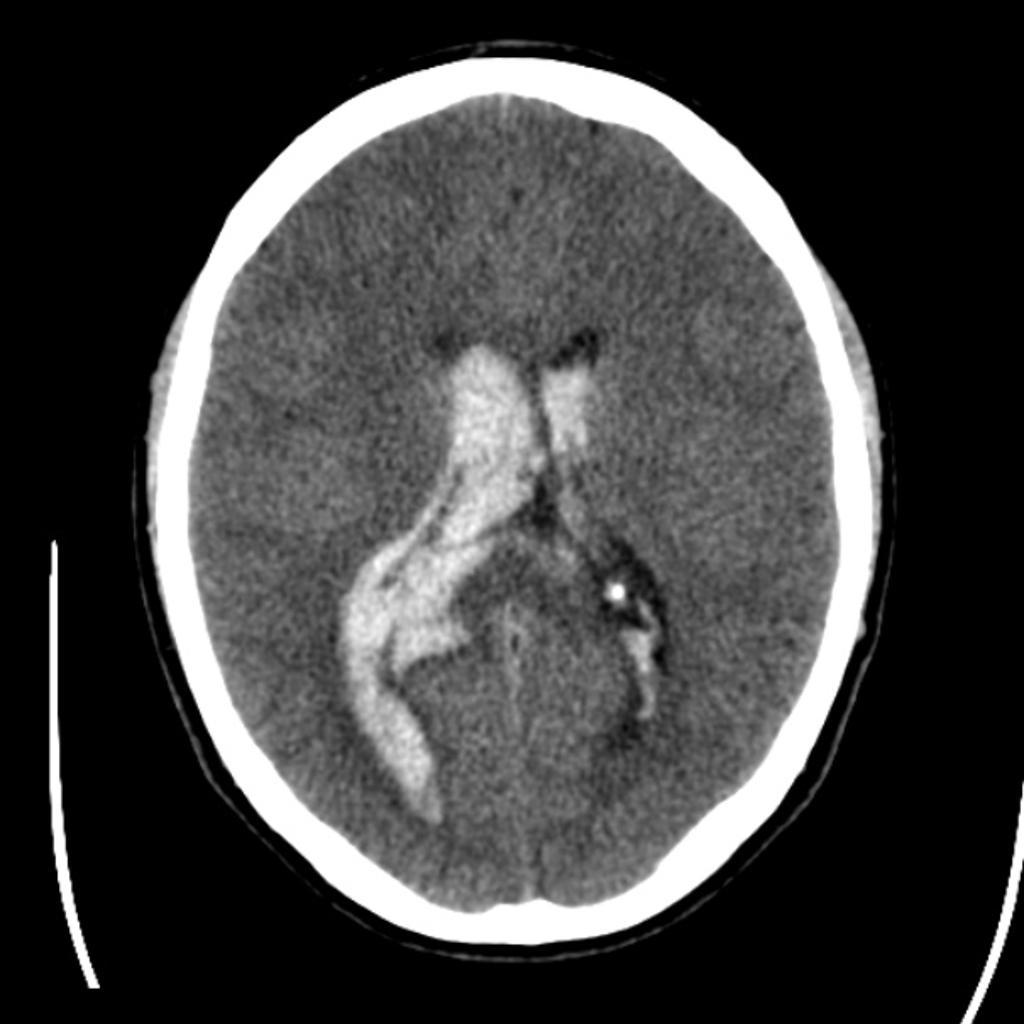

Intraventricular Hemorrhage

• Primary

• Newborns

• Secondary

• Due to SAH or intraparenchymal hemorrhage

• Presents similarly to SAH - sudden onset severe headache or stroke-like symptoms

• Hyperdense material in ventricles

• Heavier than CSF so pools dependently, best seen in occipital horns

• Often obstructive hydrocephalus, needs to be distinguished from ex vacuo dilatation of ventricles

• Ventricles: Lateral ventricles > Interventricular foramina (Foramina of Monro) > 3rd ventricle > Cerebral aquaduct (Aquaduct of Sylvius) 4th ventricle

• 3rd ventricle is located between the thalami

• 4th ventricle is located posterior to the pons and upper half of the medulla oblongata